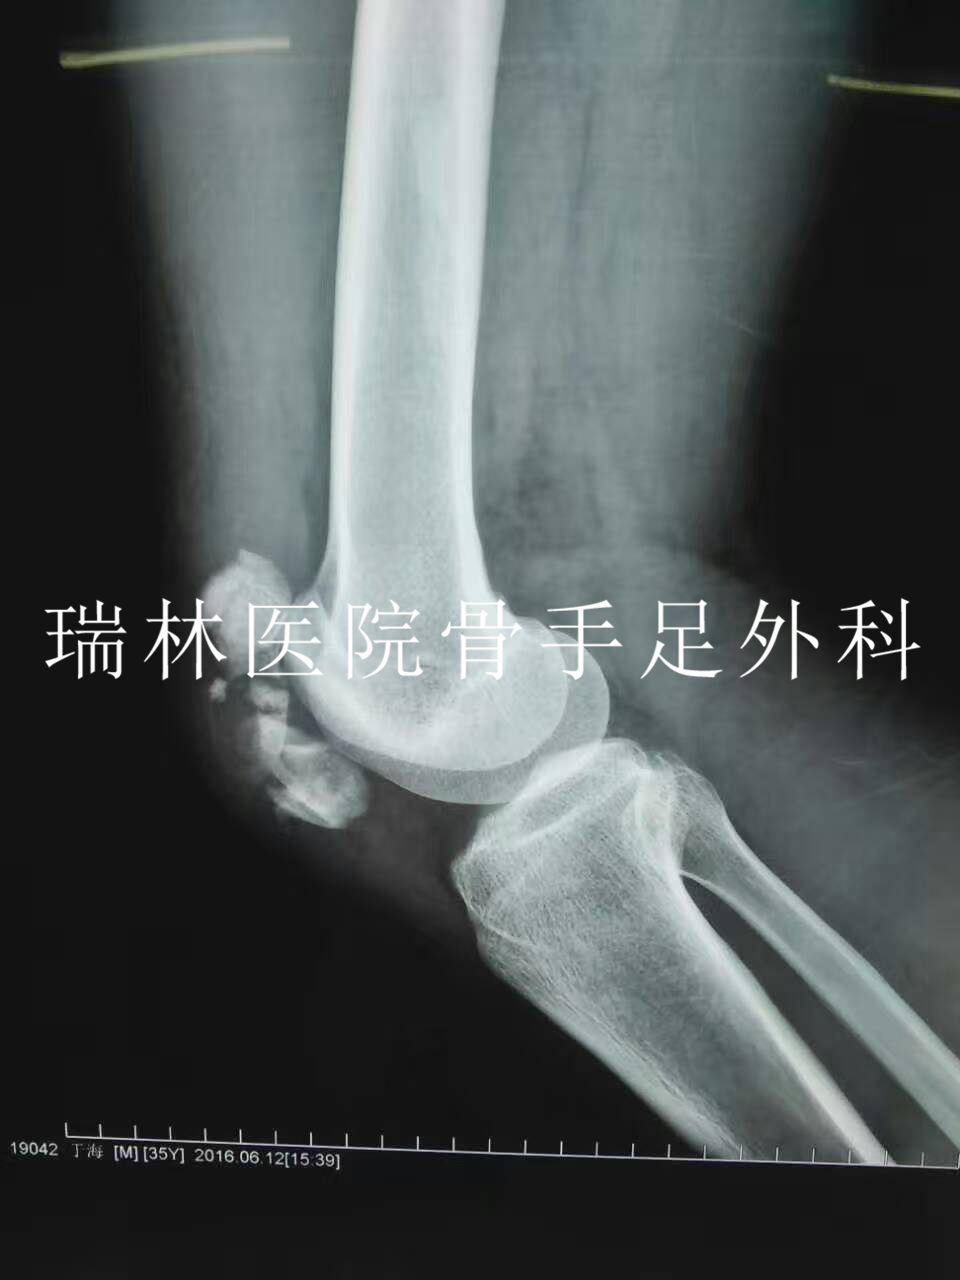

郭XX断肢再植成功

断肢再植